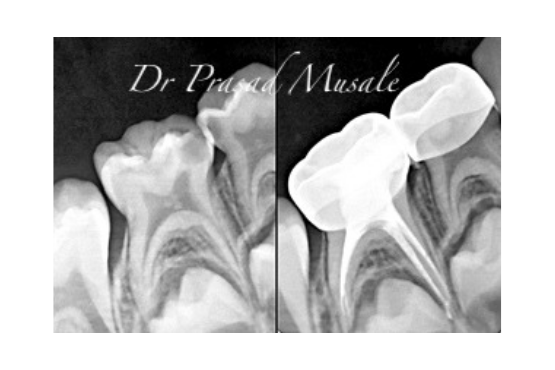

When the decay is deep and has infected the entire nerve tissue, we clean all the infected nerve inside the tooth and replace the space with medicated paste followed by a stainless steel crown.